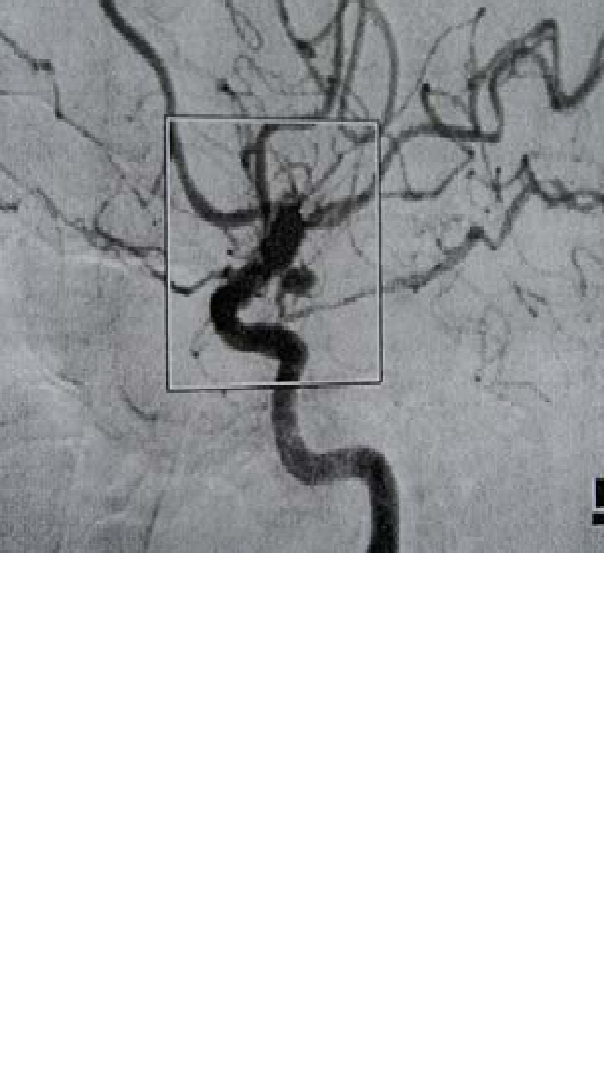

Seorang perempuan usia 54 tahun dibawa ke ruang gawat darurat setelah jatuh pingsan saat bekerja . Dia tersadar dan dapat berko-munikasi, dengan sakit kepala berat, fotopobia, nuchal kaku dan pandangan buram. CT atas otak mengungkapkan adanya darah subaraknoid menyebar pada cistern basal, Hidrosepalus ringan dan tidak tampak hematoma intraparenkimal. Angiogram pasien tampak pada Gambar.